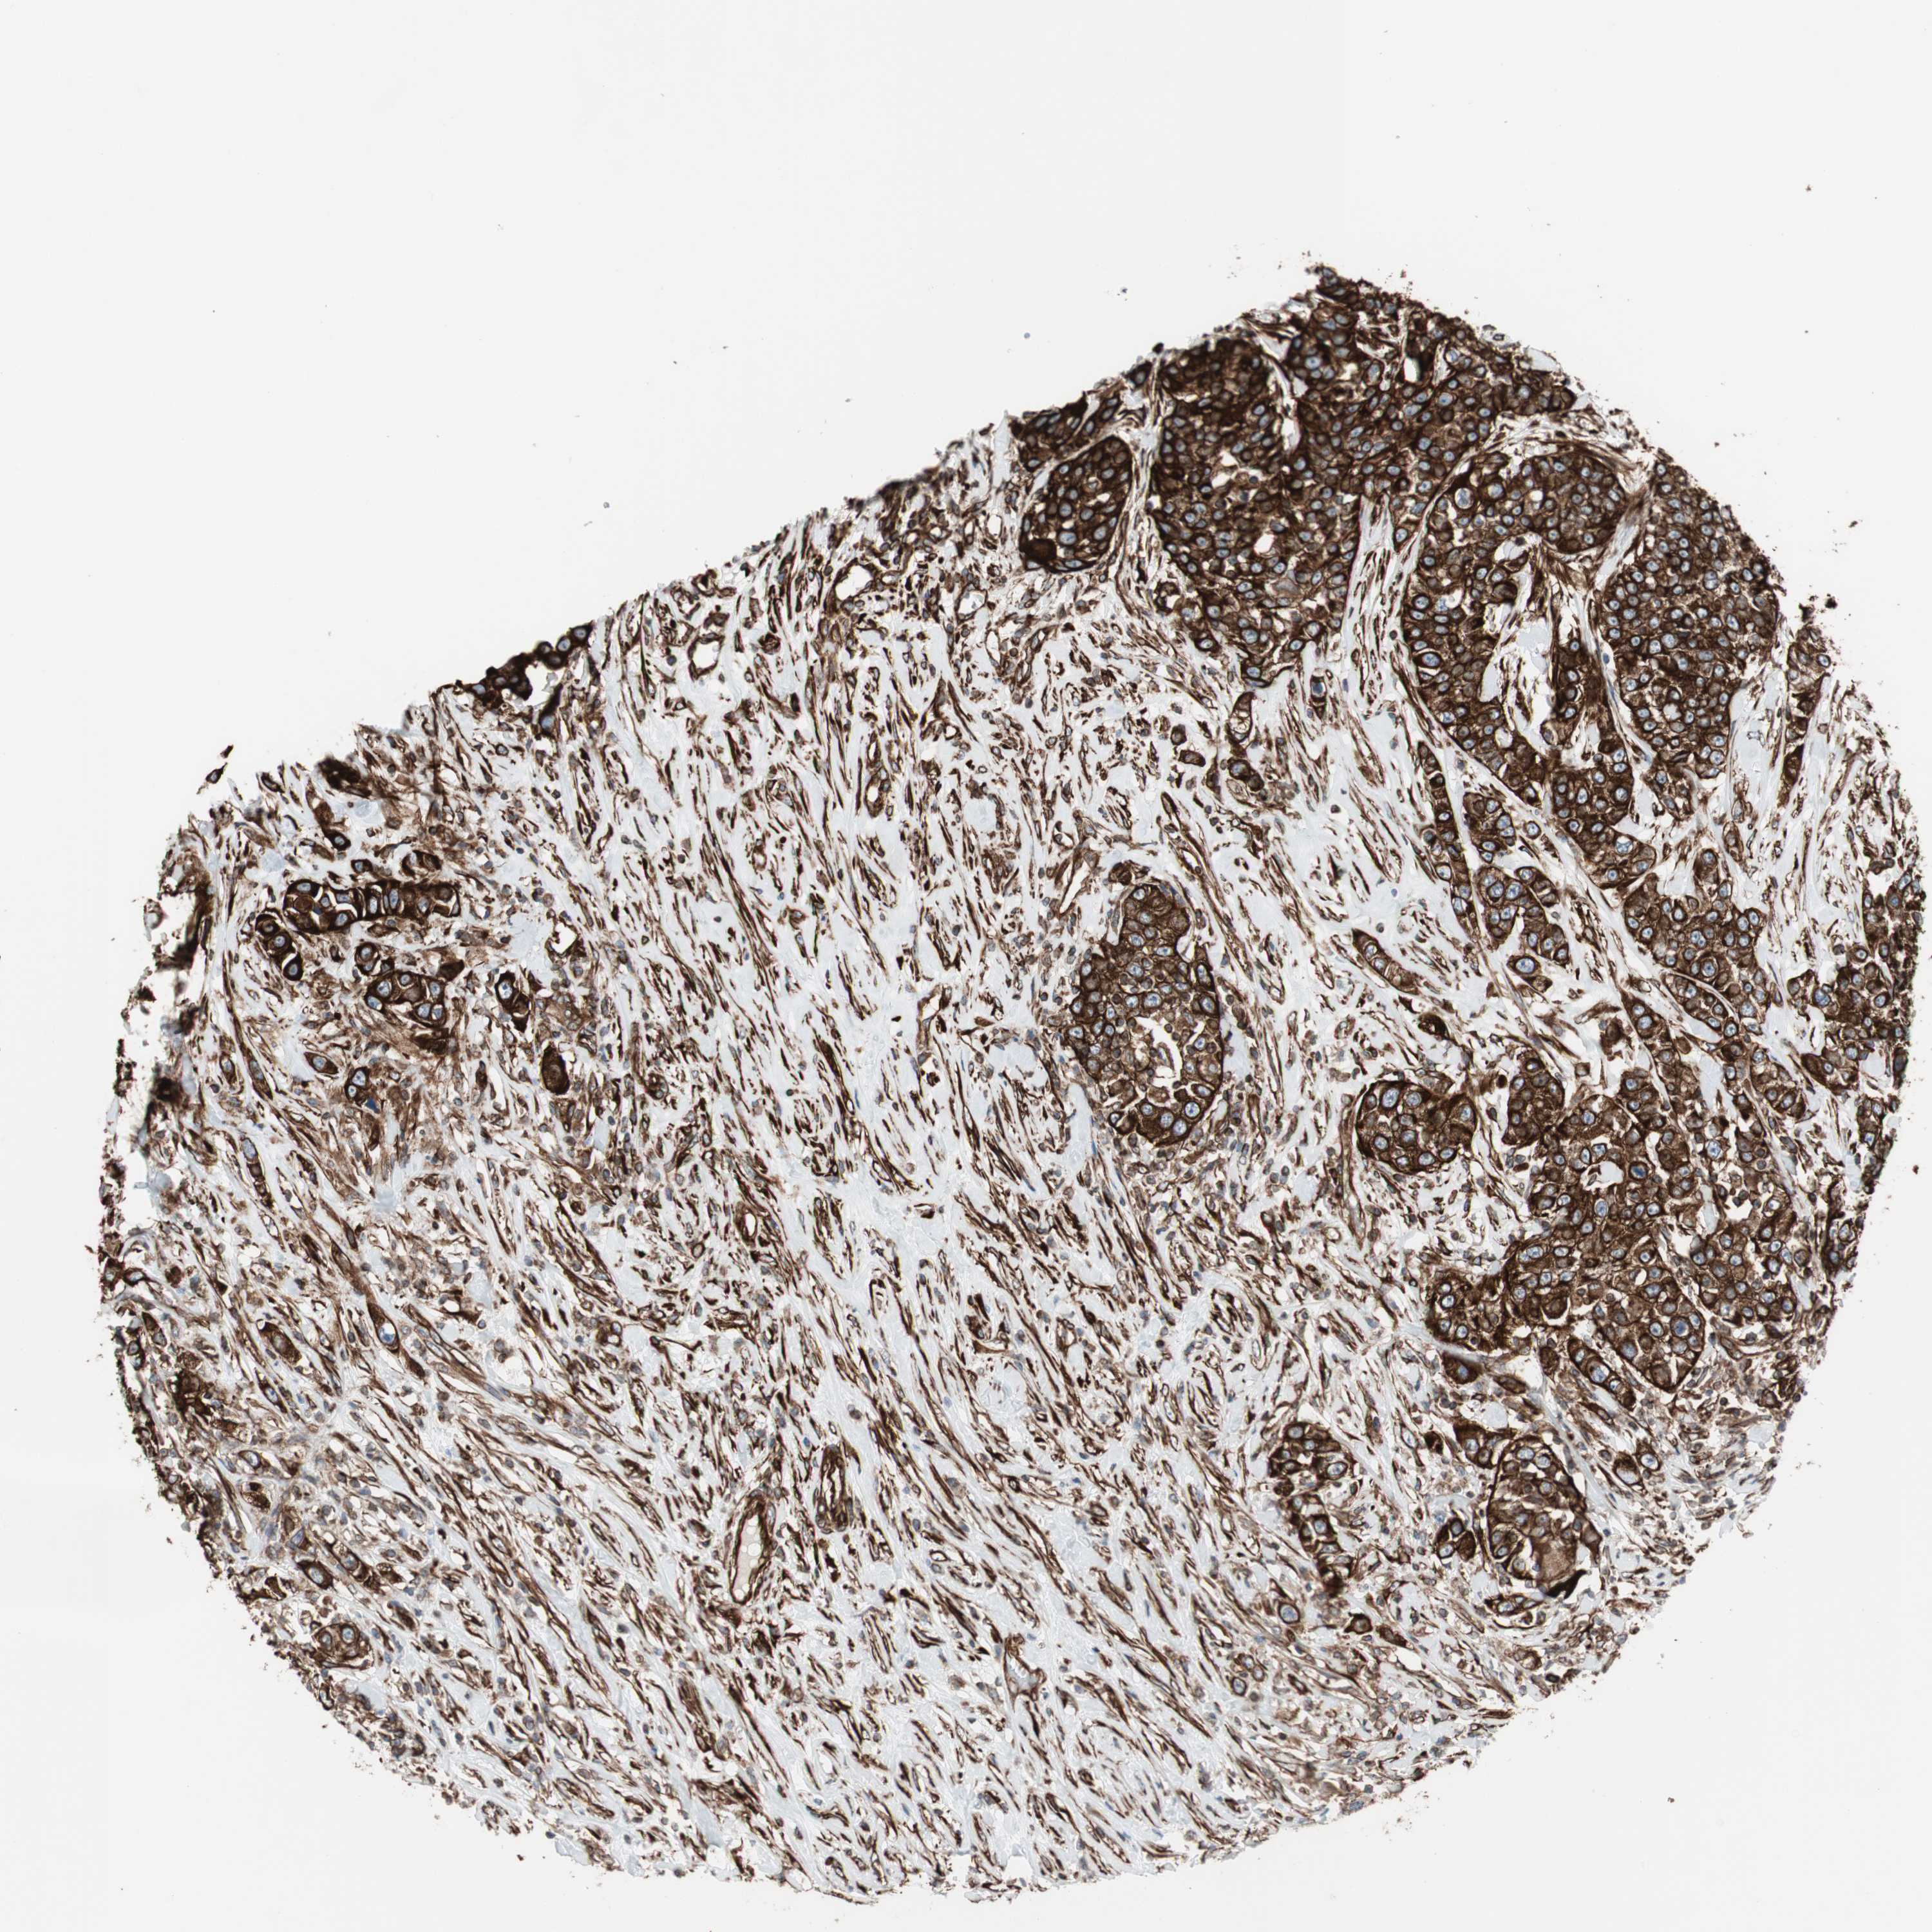

UROTHELIAL CANCER - Protein expressioni

A mouse-over function shows sample information and annotation data. Click on an image to view it in a full screen mode. Samples can be filtered based on level of antibody staining by selecting one or several of the following categories: high, medium, low and not detected. The assay and annotation is described here.

Note that samples used for immunohistochemistry by the Human Protein Atlas do not correspond to samples in the TCGA dataset.

Antibody stainingi

Antibody staining in the annotated cell types in the current human tissue is reported as not detected, low, medium, or high, based on conventional immunohistochemistry profiling in selected tissues. This score is based on the combination of the staining intensity and fraction of stained cells.

Each image is clickable and will lead to virtual microscopy that enables deeper exploration of all samples and also displays staining intensity scores, fraction scores and subcellular localization as well as patient and tissue information for each sample.

Antibody HPA007342

Staining

High

Medium

Low

Not detected

Intensity

Strong

Moderate

Weak

Negative

Quantity

>75%

75%-25%

<25%

None

Location

Nuclear

Cytoplasmic/membranous

Cytoplasmic/membranous,nuclear

Urothelial carcinoma, High grade

Urothelial carcinoma, Low grade